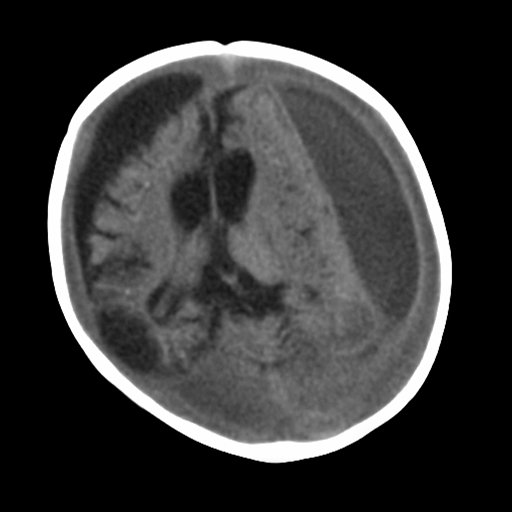

[Figure caption and citation for the preceding image starts]: MRI depicting subdural hygromas surrounding severe brain atrophy from abusive head trauma. This child was initially erroneously diagnosed with meningitisFrom the personal collection of Alice Newton, MD; used with permission [Citation ends].